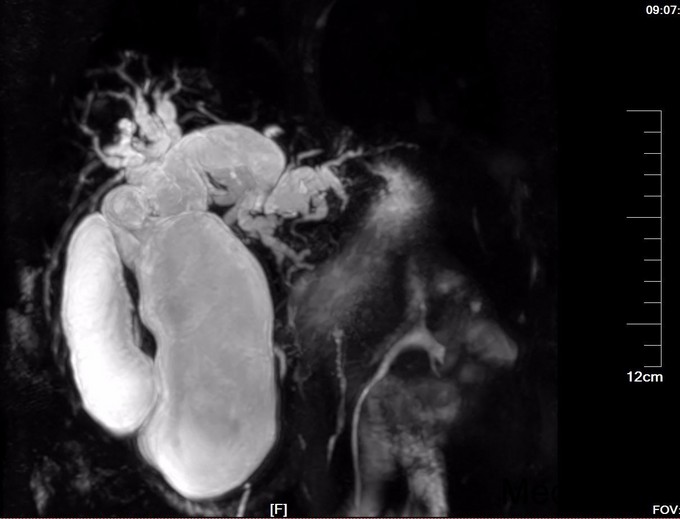

查体:腹部略膨隆,未见胃肠型及蠕动波,未见腹壁曲张静脉,右上腹部压痛阳性,无反跳痛或肌紧张,未及包块,肝脾肋下未及,Murphy氏征阳性,肝区扣痛阳性,肾区无扣痛,肠鸣音减弱,约4次/分,未闻及气过水声。 辅查: MR平扫+增强:肝脏大小形态未见异常,各叶比例正常,未见异常信号灶。肝内胆管、胆囊管及胆总管多发囊状扩张,胆总管直径6cm左右,壁厚且明显强化,腔内点状T2WI低信号影。胆囊饱满,其内可见聚集点状低信号影,胆囊壁增厚且明显强化。门脉血管显示清楚,走行正常。胰腺形态信号未见异常,胰管未见扩张。脾脏不大。增强扫描未见异常强化病灶。 MRCP:胆囊体积增大,肝内胆管、胆囊管及胆总管多发囊状扩张。胰管显影,形态走行未见异常。 CT 胆总管囊状扩张,囊壁较厚,前壁见点状钙化,较宽处直径约6.7cm,胆总管末端壁增厚,管腔狭窄;增强扫描扩张胆总管壁明显强化。肝内胆管扩张,胆囊增大,胆囊壁增厚、强化尚均匀,囊内未见异常密度影。 肝内未见异常密度影。胰腺形态、密度未见异常。脾不大。腹膜后未见确切肿大淋巴结影。

诊断: 胆总管囊肿 治疗:全麻下手术治疗。术中探查,见胆囊大10x6x4cm,肝门部可触及肿大胆总管,直径约6cm,向下延续到胰腺段,切除胆囊,于肝总管横断,向下剥离胆总管,直至胰腺段,仔细分离胆总管与胰腺,避免胰腺组织破碎,直到胆总管变细部位,切断之,远端缝扎,继续行肝管空肠Roux-en-Y吻合术。术后病理胆总管绒毛管状腺瘤,伴高级别上皮内瘤变,有恶变趋势,慢性胆囊炎。

术后检测引流液淀粉酶,术后第一天引流液淀粉酶583U/L, 按照血淀粉酶正常值3倍定义胰瘘,存在胰瘘,术后第4日272 U/L,术后7日118 U/L,已经正常。复查腹部CT, 上腹壁见手术瘢痕影,腹壁下见少量渗出、积气;肝内胆管仍扩张、程度较前减轻,胆囊未见显示,胆囊窝留置导管、局部积气。胆总管囊肿病因不清,对此假说繁多,大多数病例被认为是先天性发育不良所致。胆管壁薄弱有认为管壁的支撑组织存在先天性缺损或存在异位胰腺组织使管壁处于低张状态;胆总管远端梗阻,致管内压力增加从而引起扩张。 分为三型:普通型,憩室型,十二指肠内胆总管膨出,本病例属于普通型。临床表现为间歇性上腹痛、右上腹肿块和黄疸,称为胆总管囊肿三联征,本病例无黄疸。一旦作出诊断,即应采取手术治疗,内引流为宜。胆总管囊肿不手术,会继发结石,并且恶变,本病例经过病理证实已经出现恶变倾向,早期尽快明确诊断,及时手术治疗是此病预防的关键。